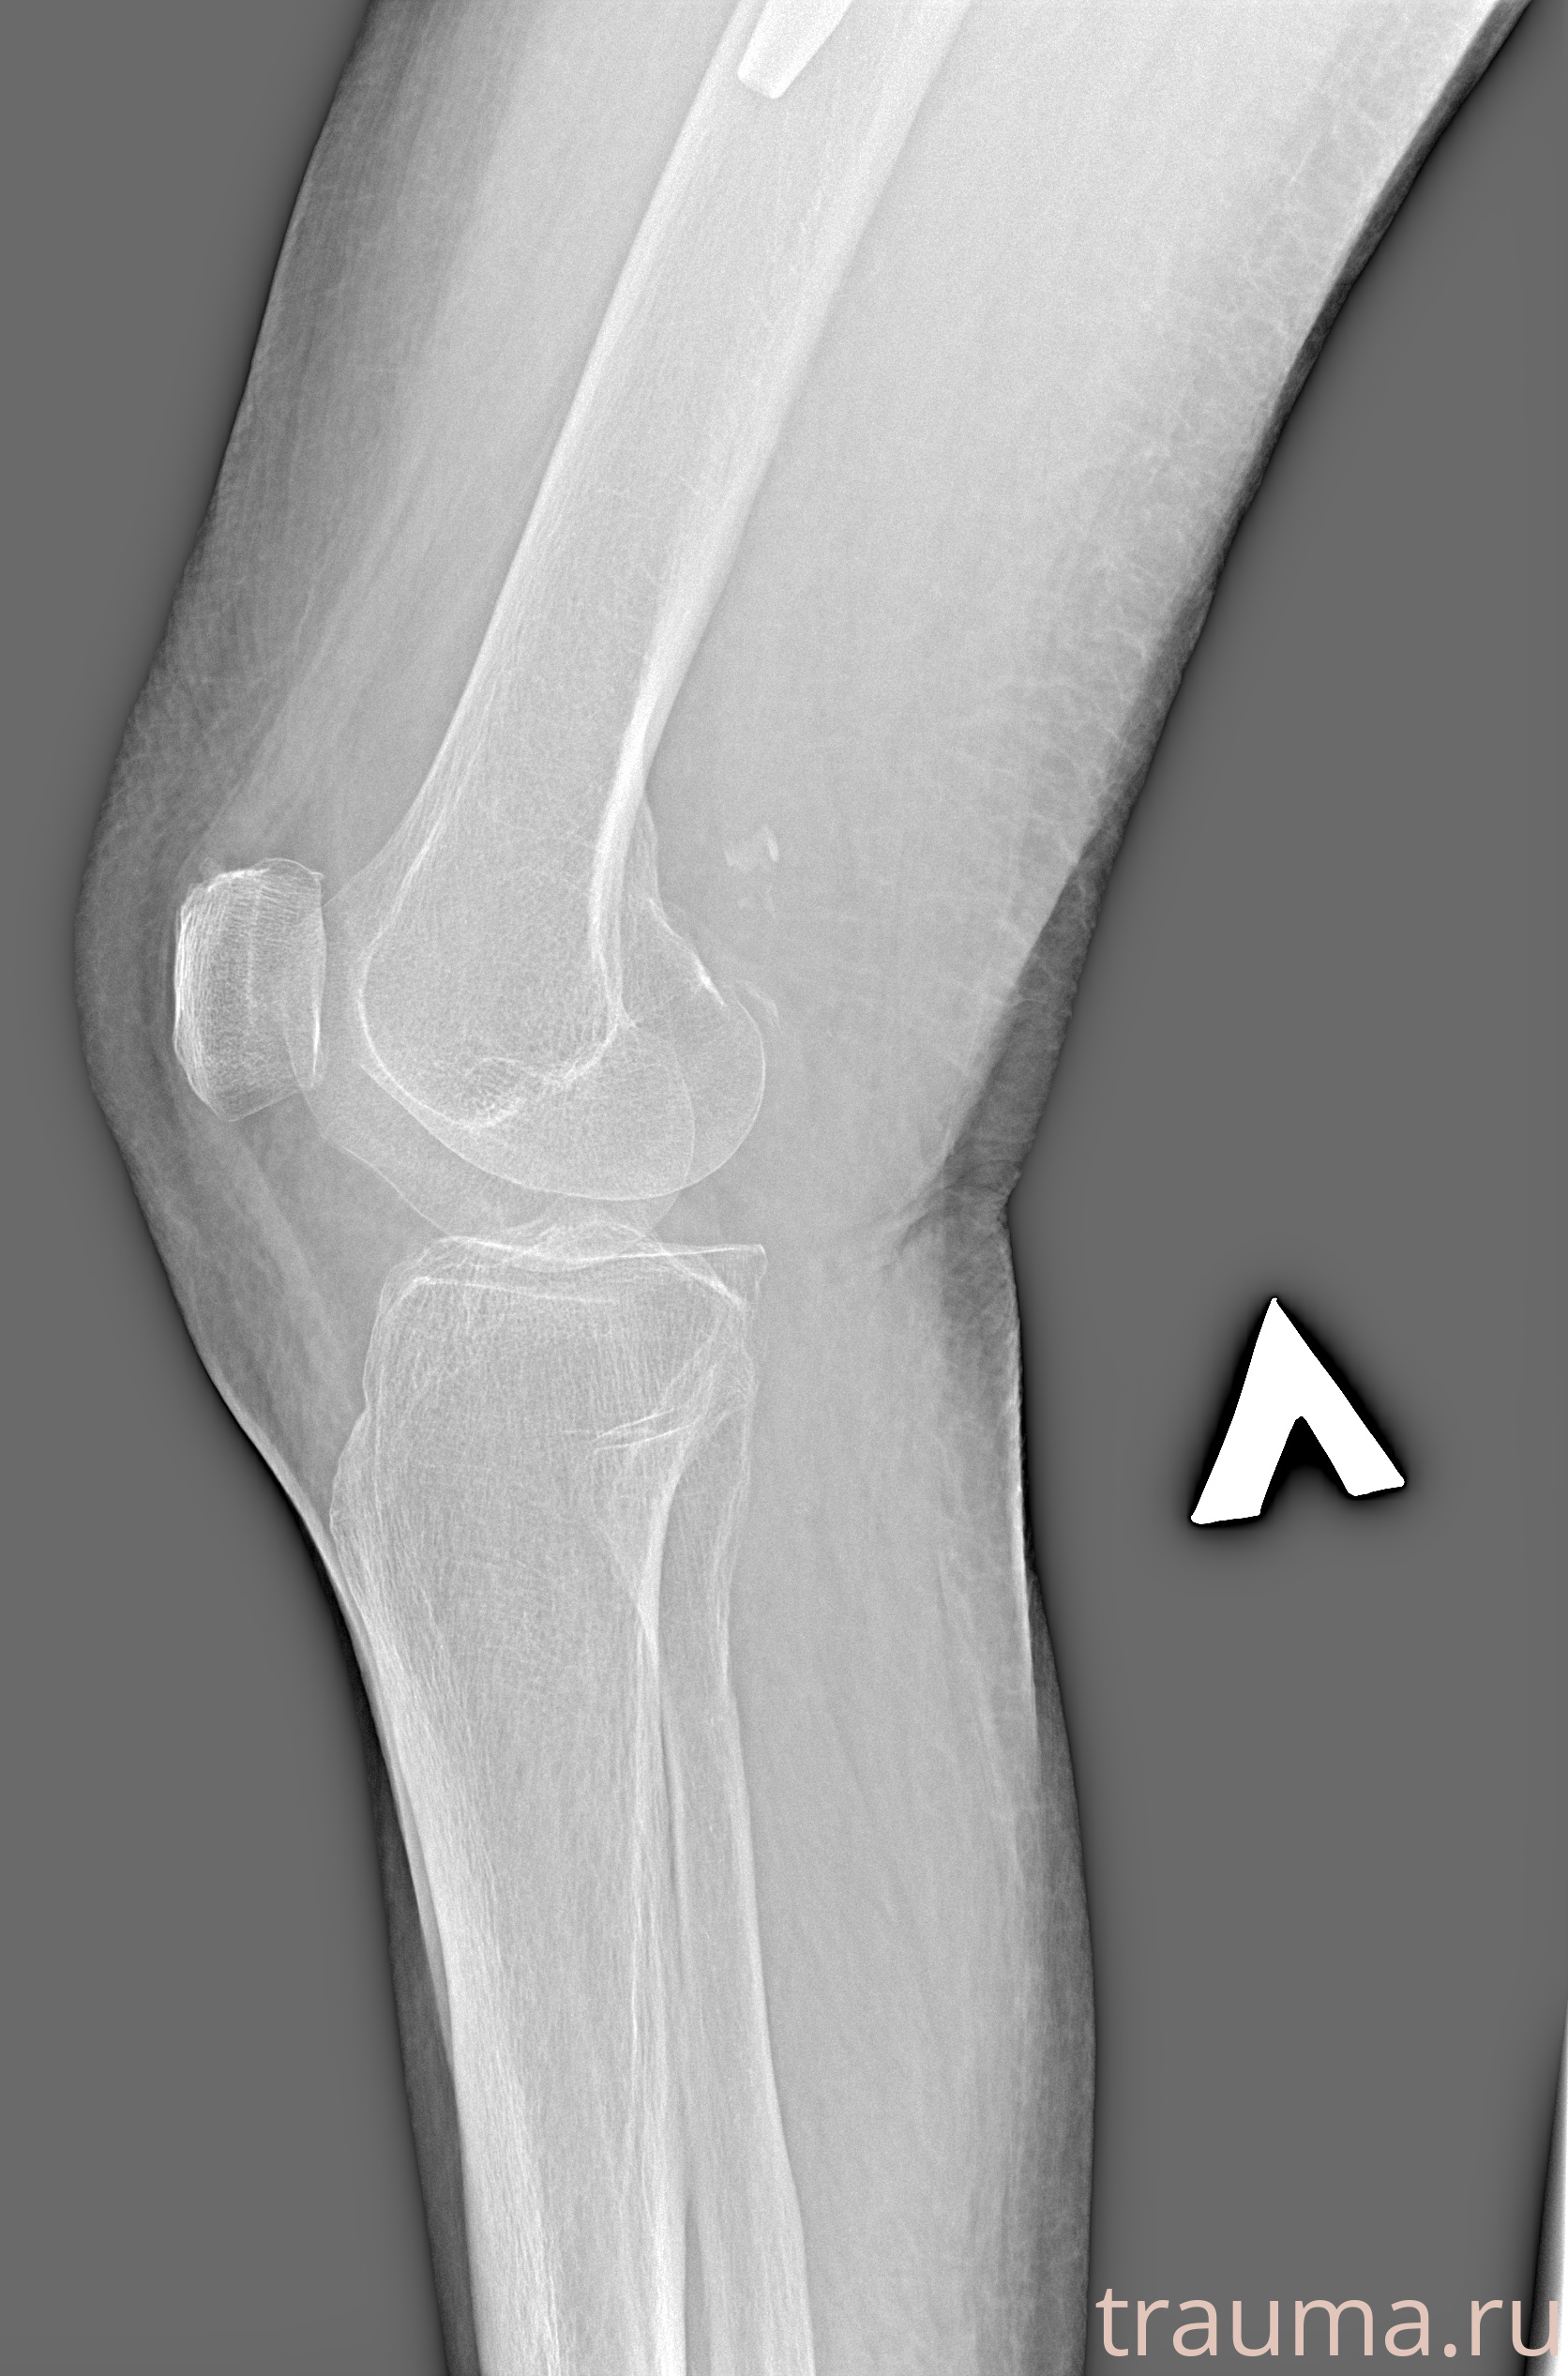

Рентгенограммы